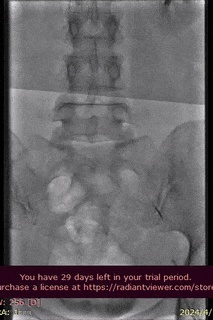

病例分享

山西省人民医院使用分享。

病例介绍

术前诊断及治疗

手术过程